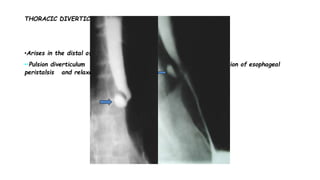

THORACIC DIVERTICULUM

•Arises in the distal of the esophagus, just above diaphragm

••Pulsion diverticulum (arrow) that probably related to incoordination of esophageal

peristalsis and relaxation of the lower esophageal sphincter